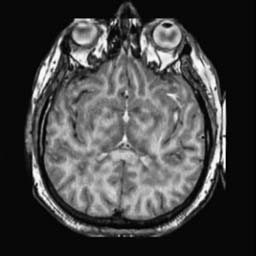

To demonstrate the effectiveness and efficiency of the proposed image fusion method , we conduct a set of comparative experiments on three image datasets. The first is composed by 8 pairs of multi-modal medical images and the second one contains 15 pairs of multi-focus gray or color natural images. These two datasets are often used in many related papers and some examples are shown in Figure 3(a) and Figure 3(b). The third one is a new multi-focus cervical cell image dataset collected by ourselves, which consists of 15 groups of color images and each group contains a series of multi-focus cervix cell images with size of or , etc. Some source examples are shown in Figure 3(c). Our source code implemented in C++ along with the new multi-focus cervical cell image dataset is available online.

We first evaluate the performance of the proposed method under varying total number of octaves and number of layers sampled per octave. The fused images of a pair of multi-modal medical images with different and are shown in Figure 4. In this example, on the one hand, when only 1 or 2 octaves are involved in constructing the DoG pyramid, the fused images fail to keep the integrity information of large size objects (e.g. eyeballs), while by increasing the value of , the integrity information of eyeballs is preserved. On the other hand, although not as significant as the increase of octave numbers , the fused image can contain more details by the increase of layer numbers . The corresponding objective quality metrics are shown in Figure 5. As shown in Figure 5(a), most of the metric values are improved as the number of octaves increases with the fixed layer numbers 3 in the global tendency and each of them tends to be stable when the number of octaves is 5. To get a relatively good quality from Figure 5(b), we can notice that some of the metric values can get a good performance when the number of layers is 3, such as the MI, SSIM, QI and VIF, though there are only a little change of all the metric values by increasing the number of layers with the fixed octave numbers 5. Because it will result in more computation burden with the increase of the value and , and for different kinds of source images, there are different performance with the diverse parameter settings. To get a trade-off between them in our experiments, we set for the multi-modal dataset, for the natural datasets and for the multi-focus cell dataset, respectively.

Figure 6 shows the fused images obtained by different methods with the multi-modal source images shown in Figure 3(a). As shown in these figures, the proposed method can produce images which preserve the complementary information of different source images well. Moreover, due to the scale-invariant structure saliency selection, our method can keep the integrity information of large size objects and the visual details simultaneously. Although the fused image generated by other methods can also capture the details to some extent, all of them fail to keep the integrity information of large size objects such as the eyeballs. Furthermore, from Figure 6(k)-6(t), the DTCWT, GFF, IM and NSCT methods may decrease the brightness and contrast while the proposed method can preserve these features and details without producing visible artifacts and brightness distortions.